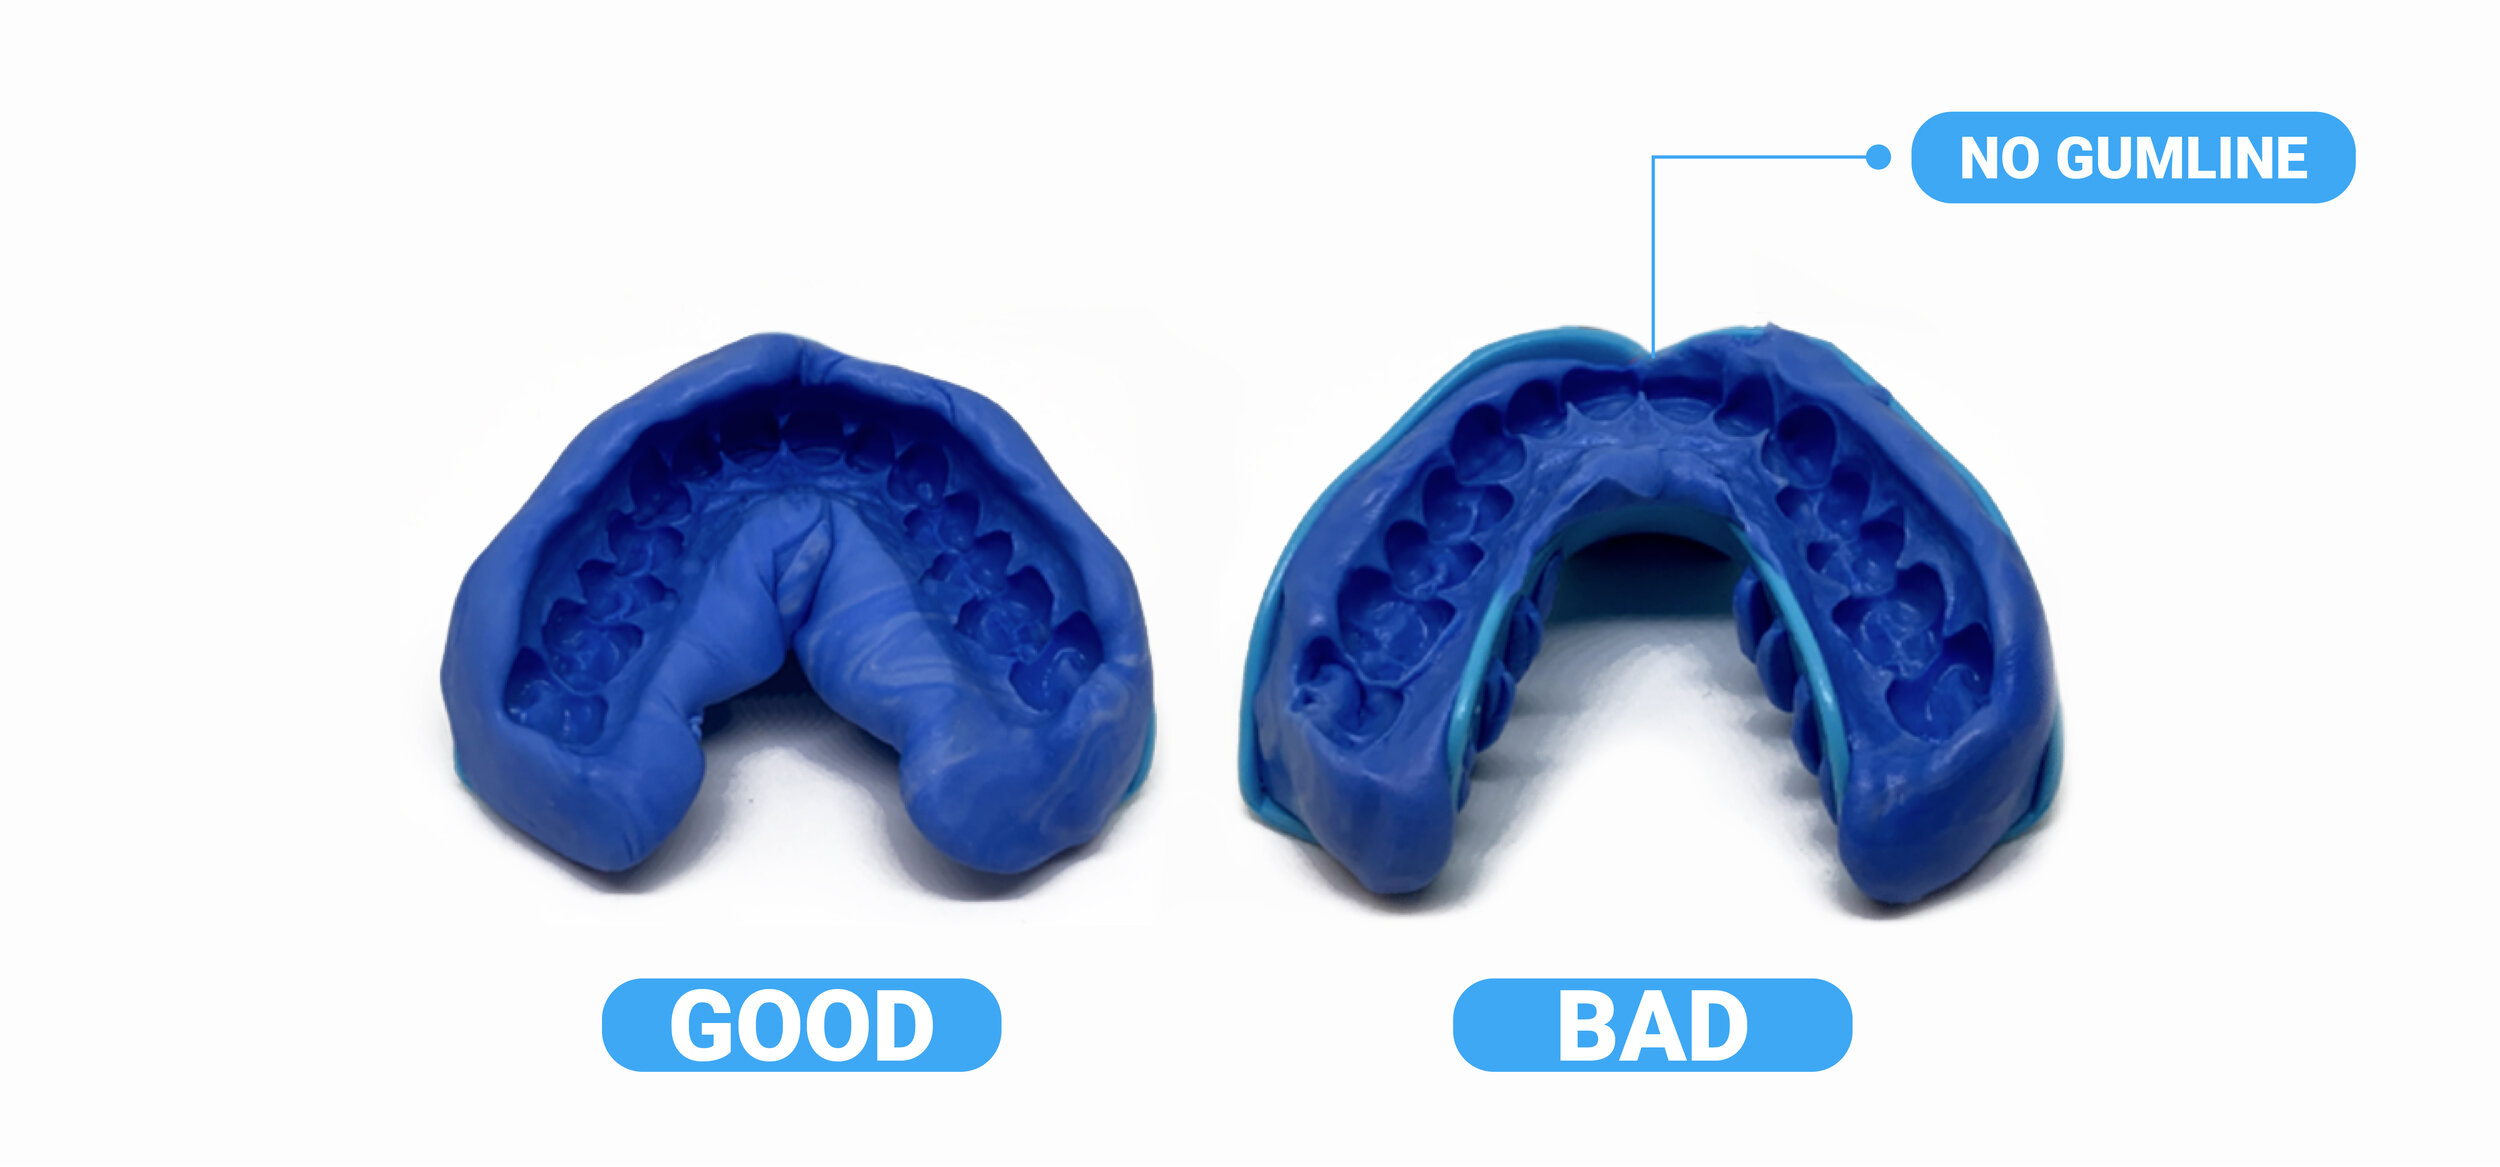

Taking Impressions

Taking Impressions

Taking Impressions

Taking Impressions

Taking Impressions

Taking Impressions

Taking Impressions

Taking Impressions

Taking Impressions

Taking Impressions

Taking Impressions

Taking Impressions

Taking Impressions

Taking Impressions

Taking Impressions

Taking Impressions

Taking Impressions

Taking Impressions

Text

Taking Impressions

Text

Taking Impressions

Taking Impressions